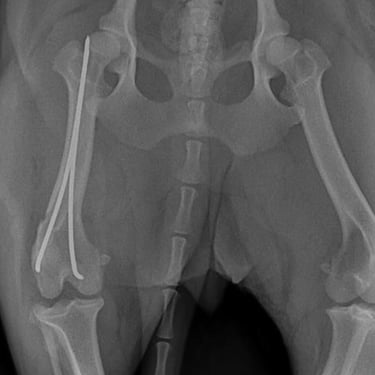

Clavos intramedulares: se colocan dentro del canal medular y proporcionan soporte principalmente contra fuerzas de flexión. Suelen utilizarse en fracturas diafisarias y, en muchos casos, se combinan con cerclajes o fijadores externos para mejorar la estabilidad rotacional.